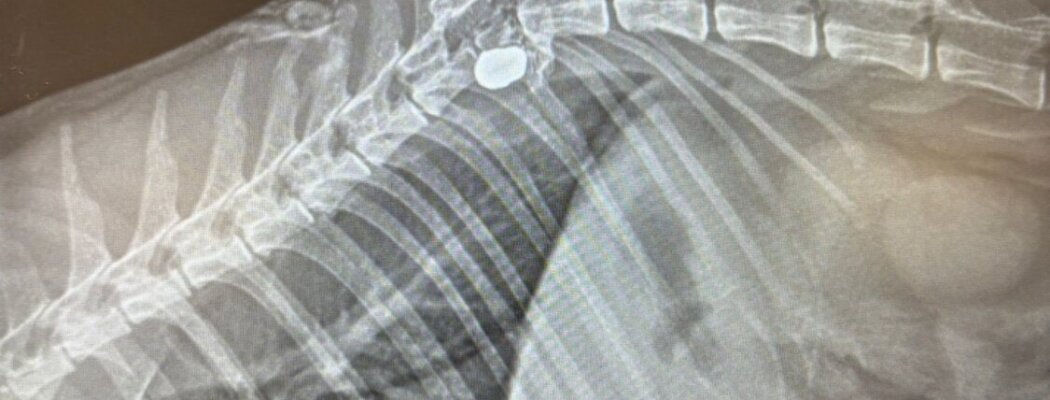

Met spoed ging het dier naar de dierenarts. Na onderzoek kwam de dierenarts met tranen in haar ogen teruglopen: een kogel had een ruggenwervel geraakt. “Je buik draait twee keer om. Wat is dit nou weer,” zegt Cornee. Er was geen andere keuze dan Pluisje in te laten slapen.